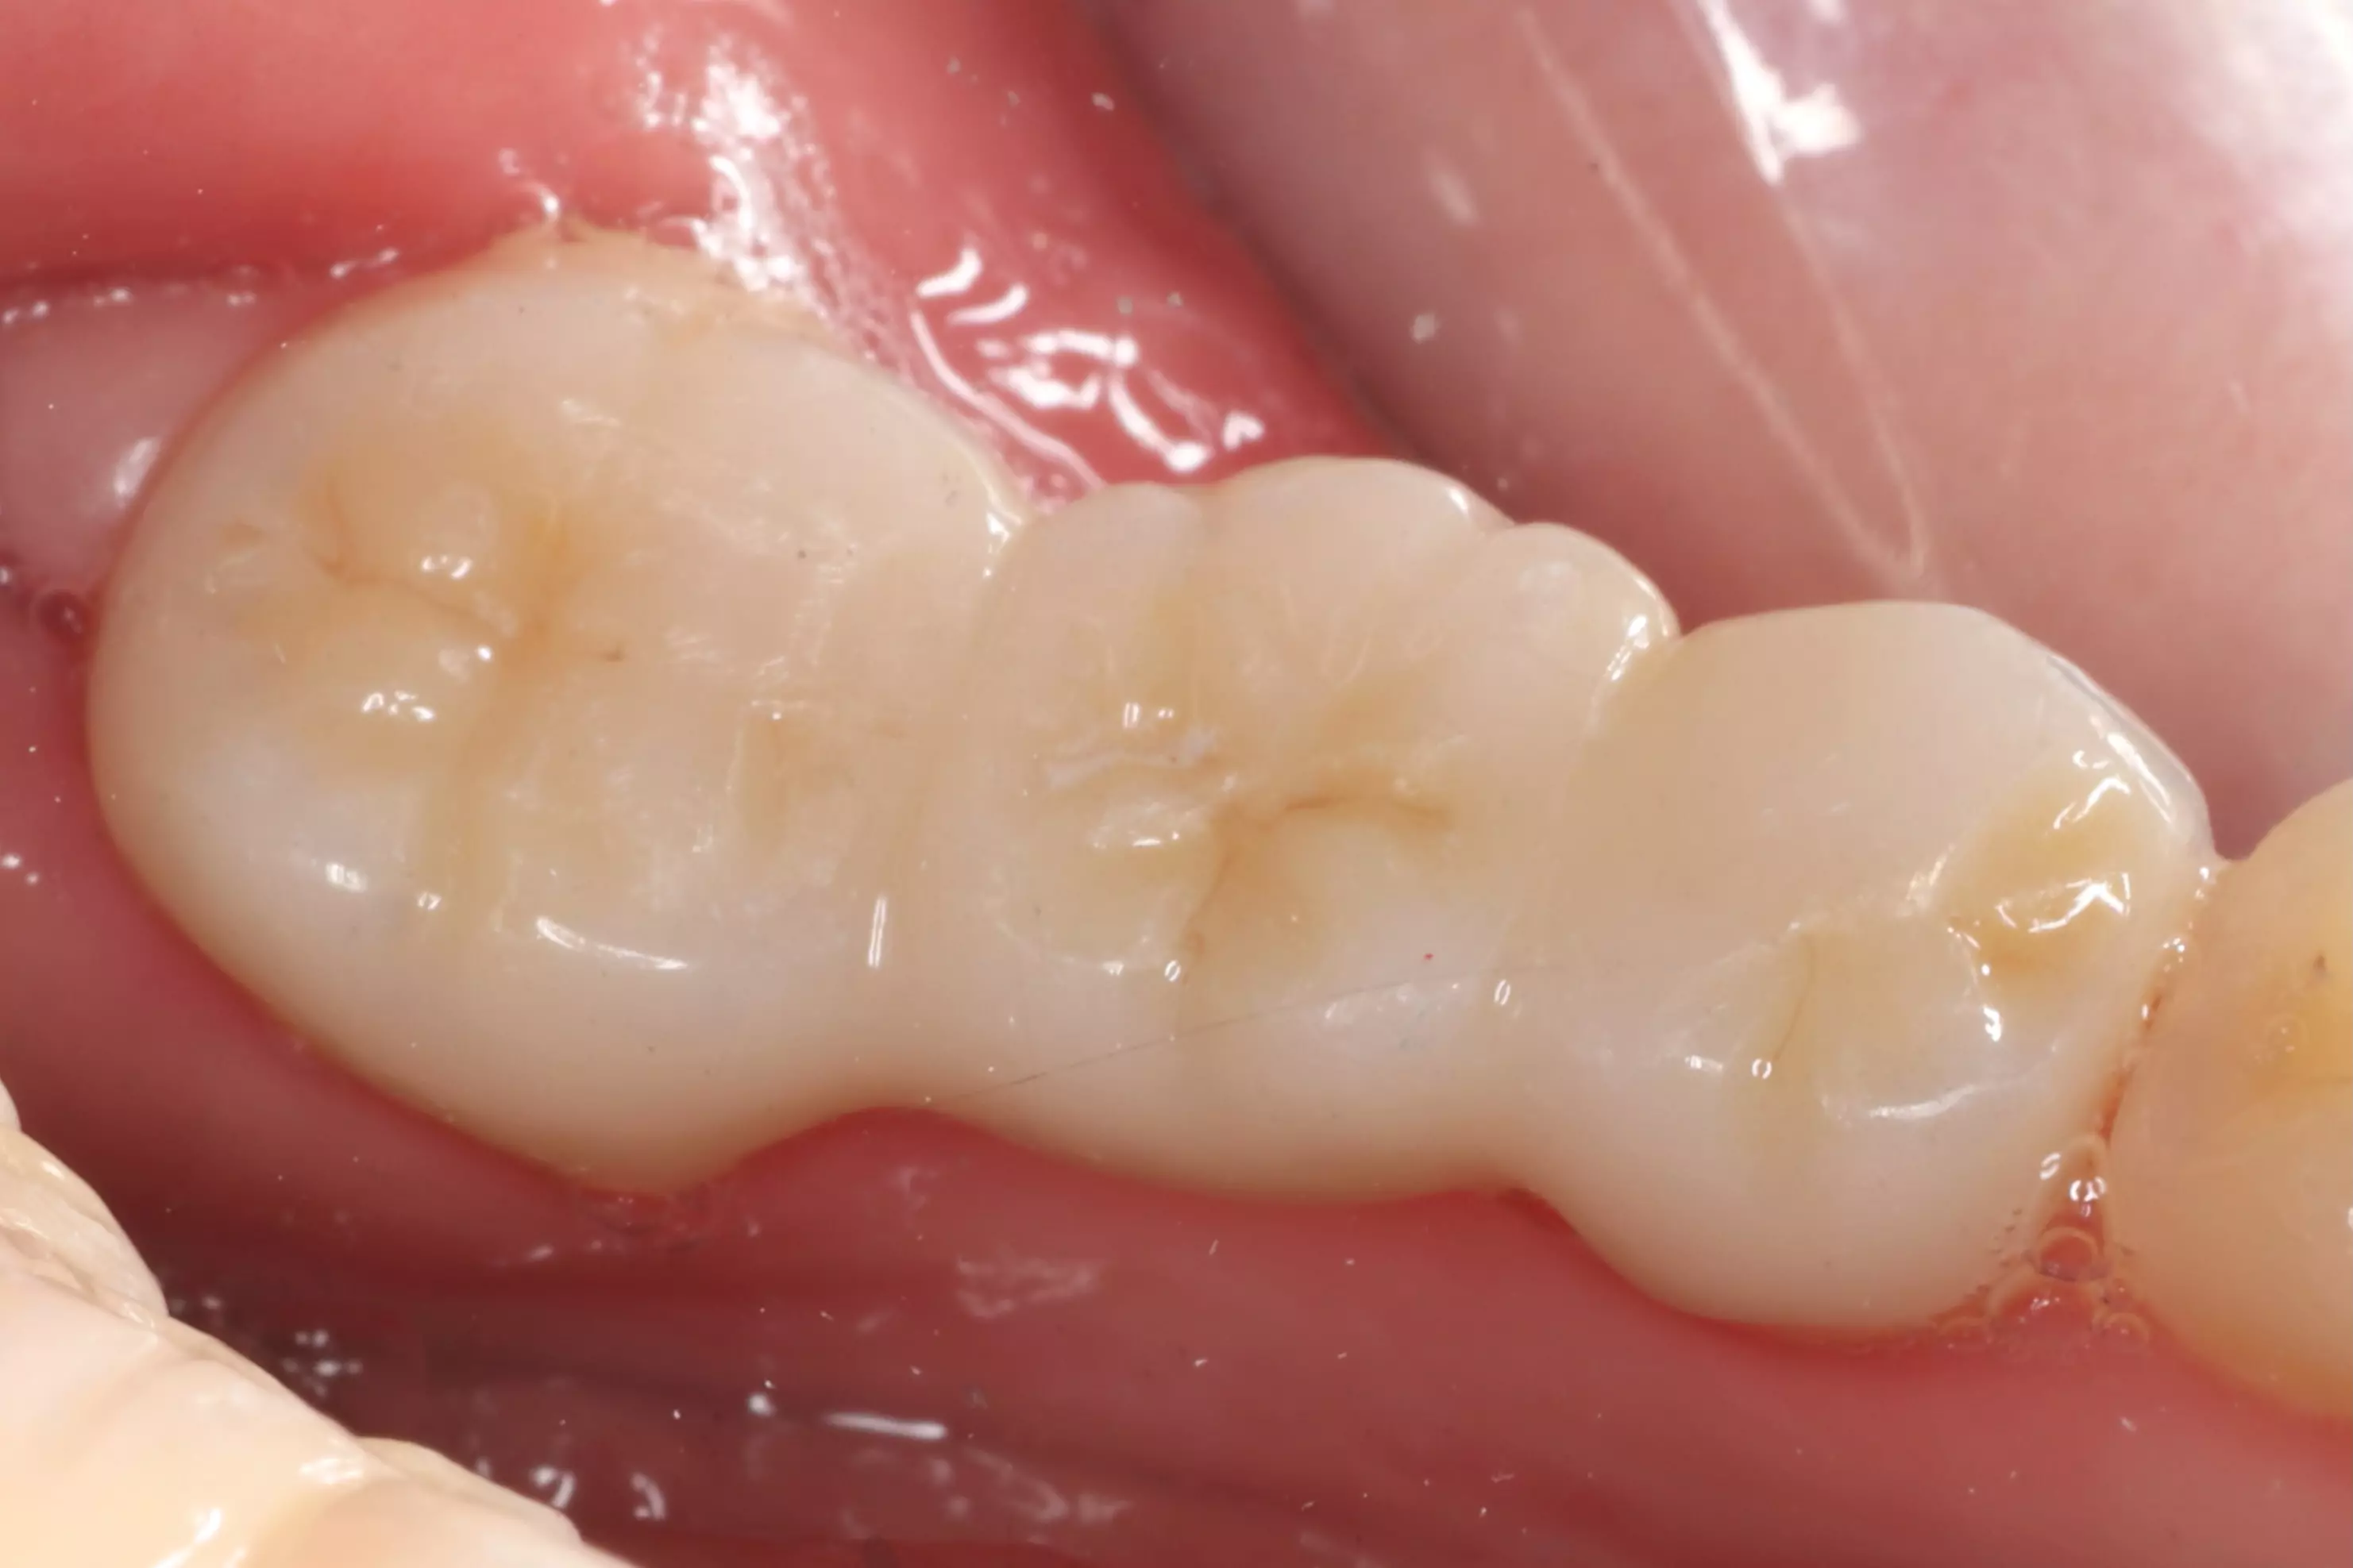

下方是治療完成的照片。歷時四個多月,在患者、家屬、及醫療團隊的共同努力下,終於完成新的假牙製作。